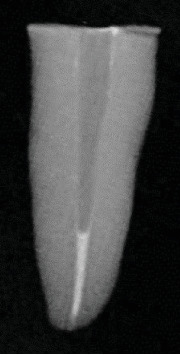

Abstract Image